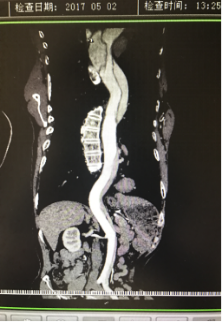

5月2號劉大伯照常早起干活,突然胸部劇烈疼痛,難以忍受,全身大汗,同時伴有右上肢發(fā)涼,他心想這次心絞痛比之前嚴(yán)重的多啊,趕緊叫上孩子到吉林國文醫(yī)院心血管內(nèi)科住院,患者長期高血壓病史,血壓一直控制不理想,大夫給他做了檢查,測左上肢血壓:82/45mmHg,右上肢血壓測不出,心率52次/分,右側(cè)肱動脈、尺動脈、橈動脈搏動消失,左側(cè)股動脈搏動較右側(cè)弱?!霸懔?,雙側(cè)血壓差別這么大,是不是主動脈夾層了?”,接診大夫趕緊找來李主任,李主任反復(fù)詢問患者病情,表情突然凝重起來,患者胸痛這么明顯,血壓低的厲害,主動脈夾層的可能性很大。二話不說,李主任立即聯(lián)系影像科的醫(yī)生準(zhǔn)備做主動脈CTA,移動患者做檢查的過程大夫們非常小心,嚴(yán)密監(jiān)測患者血壓變化情況。兩個小時后結(jié)果出來了,主動脈夾層從升主動脈一直撕裂到左側(cè)髂總動脈!??!